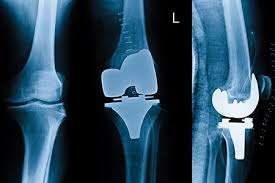

Knee Replacement Surgery in Bastar – Dr. Siddharth Jain (AIAS) MBBS, MS, DNB, FIAS (England) | Arthroscopy, Sports Injury & Orthopedic Surgeon Chronic knee pain can severely affect daily...

Knee Replacement Surgery in Balrampur-Ramanujganj – Dr. Siddharth Jain (AIAS) MBBS, MS, DNB, FIAS (England) | Arthroscopy, Sports Injury & Orthopedic Surgeon Joint pain in the knees can gradually...